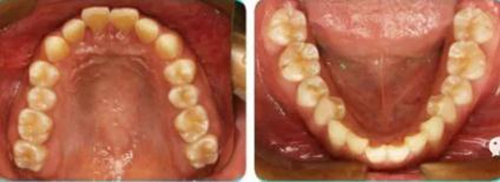

李某,女性,18歲,咬合不良要求矯治。

正面觀雙側(cè)面型基本對稱,側(cè)面觀上頜凸、下頜后縮,頦唇溝深。

恒牙列,上下牙列中線對齊,前牙深覆合、深覆蓋均為Ⅲ°。雙側(cè)磨牙、尖牙為Ⅱ類遠中關(guān)系,A4C4、B4D4正鎖合。

(1)安氏Ⅱ類1分類錯合;

(2)A4C4,B4D4正鎖合;

(3)前牙重度深覆合、深覆蓋。